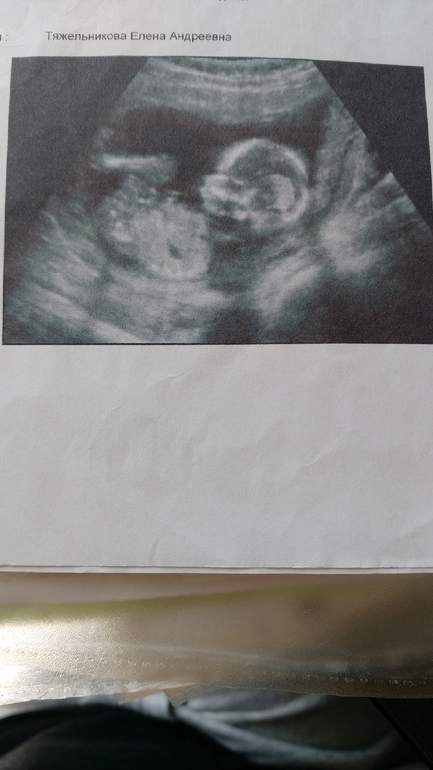

Кстати нашла тут младшую дочу, узи было на 17 неделе, если честно для меня все одиноково😄